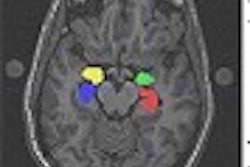

Imaging technologies like functional MRI and PET are demonstrating that meditation techniques have a profound impact on brain function. For example, one study used MRI and PET to examine Tibetan monks and found them to have more activity in their prefrontal lobes, the area of the brain associated with positive emotions.

Another study, using SPECT, found decreased brain activity during meditation in the parietal lobe -- the area that controls our sense of orientation in time and space. The researchers believe the findings reflect a blocking of sensory and cognitive input into the parietal lobe, which would account for the detachment from time and space experienced by many who meditate.